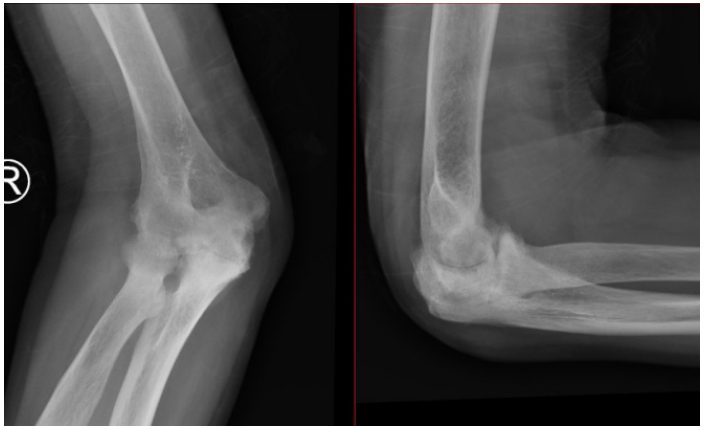

周伯的术前肘关节X线

经过一段时间的治疗,肿胀和疼痛虽有所缓解,但他的右肘却再也无法完全伸直。更令人揪心的是,近四年来,他的右臂肌肉逐渐萎缩,肘关节僵硬得像锈死的门轴,连日常的吃饭、穿衣都成了折磨。持续的疼痛日夜纠缠,让他连睡一个安稳觉都成了奢望……

对于周伯这样深受终末期类风湿性肘关节炎折磨的患者——关节严重磨损变形、持续剧痛、功能几近丧失,人工肘关节置换术成为恢复关节功能和缓解疼痛的终极解决方案。